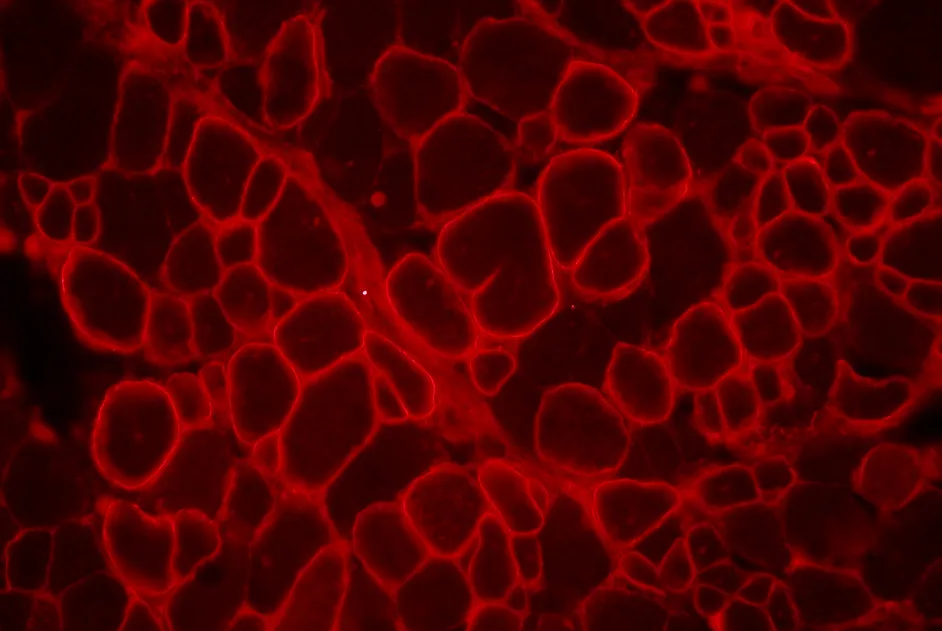

Bonne tolérance et restauration de l’expression de la dystrophine lors d’un essai de phase Ib/II du saut d’exon chez 19 sujets atteints de myopathie de Duchenne